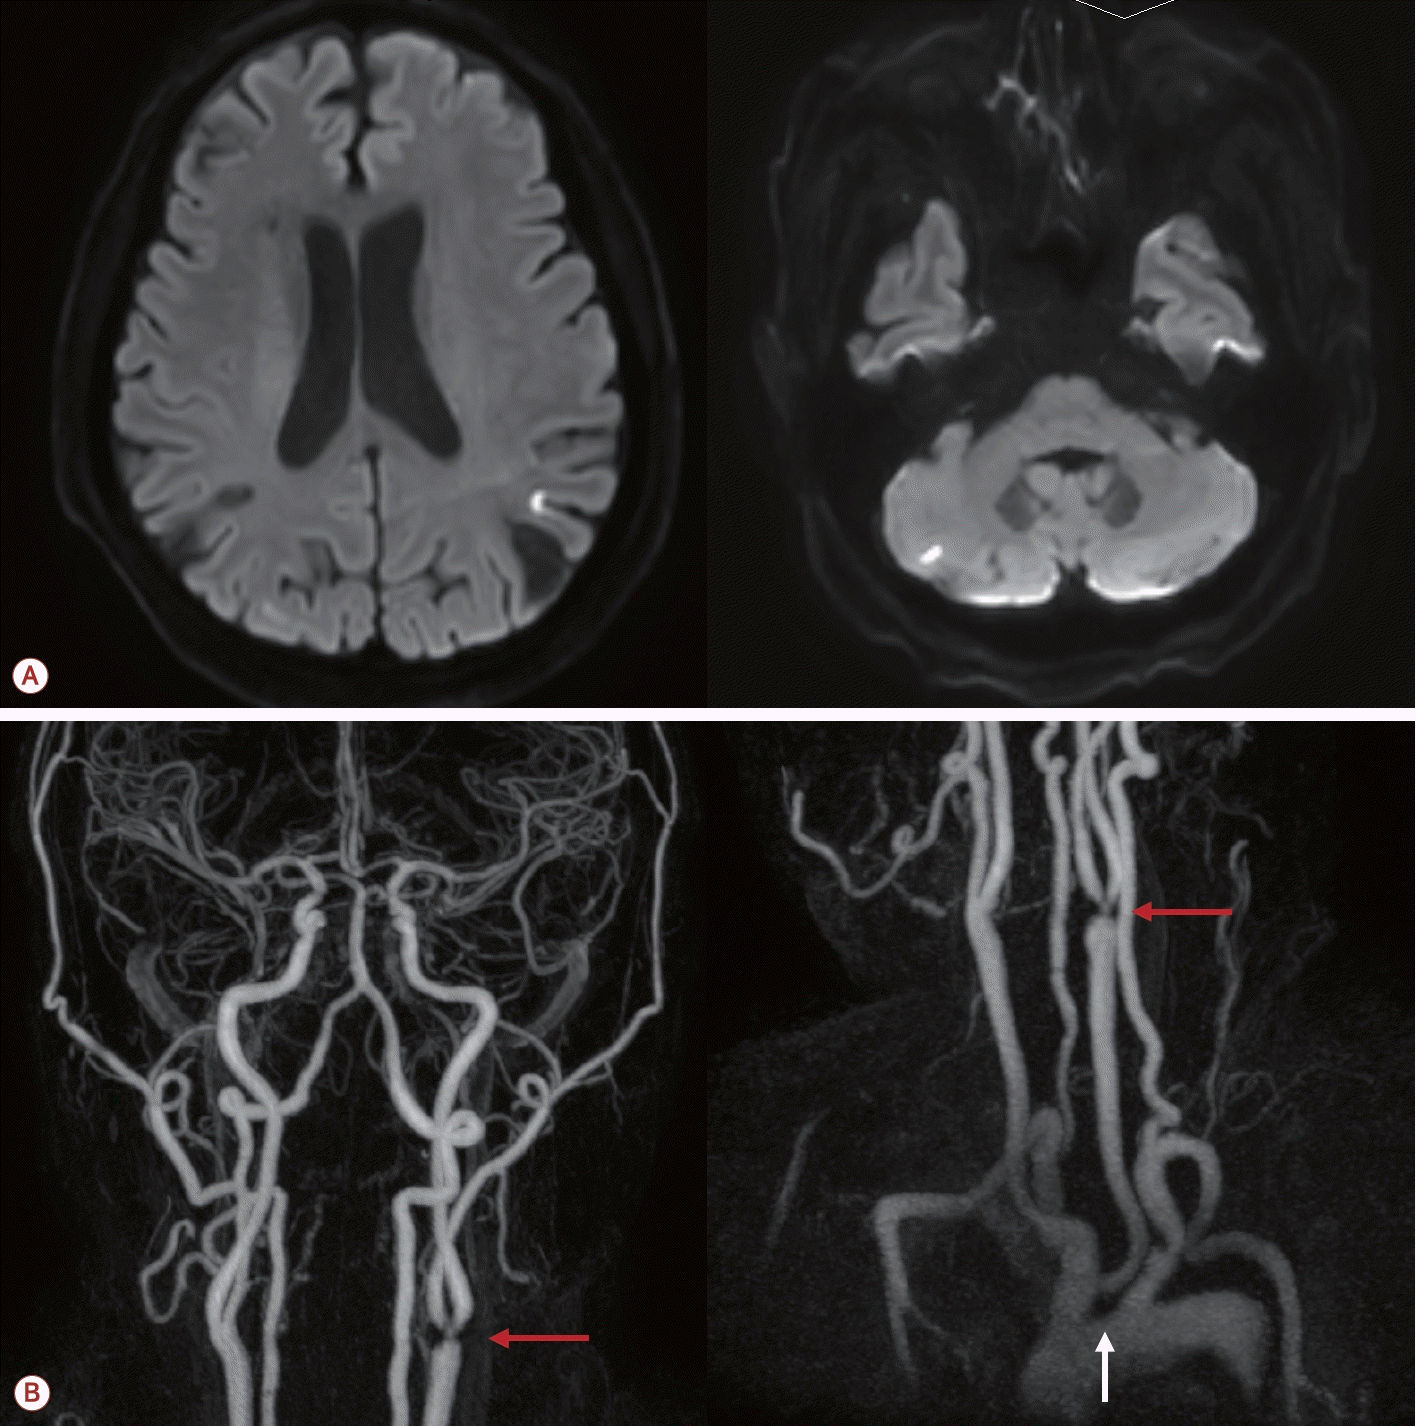

73세 남자가 최근 3개월간 반복적인 허혈뇌졸중으로 내원하였다. 환자는 고혈압, 당뇨, 안정협심증의 기저 질환을 가지고 있었다. 초기 뇌자기공명영상(magnetic resonance [MR] imaging)에서 좌측 대뇌반구와 우측 소뇌에 다발성 허혈 병변이 관찰되었으며(Fig. 1-A) 혈관 검사에서는 좌측 내경동맥근위부(internal carotid artery, ICA)에 76.7%의 협착(NASCET 기준)이 확인되었고 동시에 보바인형 대동맥궁(bovine arch, 공통 기시형 변이)이 관찰되었다(Fig. 1-B). 이에 따라 증상성 중증도 이상의 ICA 협착으로 판단하여 좌측 CEA와 이중 항혈소판 요법이 시행되었다. 그러나 시술 2개월 후에 우측 후 대뇌동맥(posterior cerebral artery, PCA)과 우측 중대뇌동맥(middle cerebral artery, MCA) 영역에 재발성 뇌경색이 발생하였고(Fig. 2-A) 한 달 후에는 좌측 MCA와 PCA 영역에 새로운 뇌경색이 재발하였다(Fig. 2-B). 기존에 진행되었던 두개경유도플러 검사에서 심방중격 결손이나 미세색전 신호를 시사하는 소견은 확인되지 않았고 흉부경유심초음파에서 좌심실 박출률은 정상 범위었으며 3일의 홀터 모니터링에서도 심방세동은 관찰되지 않아 심장성 색전은 배제하였다. 반복되는 색전성 병변의 원인을 찾기 위하여 식도유심초음파(transesophageal echocardiography, TEE)가 진행되었으며 대동맥궁 대만부(greater curvature)에 위치한 7 mm 크기의 궤양성(ulcerated), 유동성(mobile)의 고위험 죽경화판(high-risk aortic arch plaque)이 관찰되었다(Fig. 2-C). 추가적인 머리 혈관조영에서는 기존에 확인되었던 좌측 경동맥의 중증도 협착은 호전 상태를 보였으며 보바인형 대동맥궁 및 팔머리동맥에 동맥류성 확장(aneurysmal dilatation)을 확인할 수 있었다(Fig. 3-A). 이에 신경과, 순환기내과, 영상의학과, 심장혈관흉부외과가 포함된 다학제 협의를 통해 단계적 하이브리드 치료가 결정되었다. 첫 번째 단계로 부분 디브랜칭 수술(좌쇄골하-좌총경동맥우회술[partial debranching surgery, left subclavian-left common carotid artery bypass])이 시행되었다. 수술 한 달 후에 팔머리동맥에 스텐트이식편(endovascular brachiocephalic stent-graft)을 삽입하여 팔머리동맥류의 병적 분절을 제거하였다(Fig. 3-B, C). 스텐트 시술 이후 약 1년 6개월이 지난 현재까지도 환자는 지속적으로 이중항혈소판 요법을 유지하면서 추가적인 허혈 사건 없이 안정적으로 추적 관찰 중이다.

Figure 1.

(A) Initial brain MR imaging showing multiple small acute ischemic lesions in the left cerebral hemisphere and right cerebellum. (B) Initial MR angiography demonstrating 76.7% stenosis (as calculated in NASCET) of the left proximal internal carotid artery (red arrows) and bovine aortic arch (white arrow). MR; magnetic resonance, NASCET; North American symptomatic carotid endarterectomy trial, MRI; MR imaging.